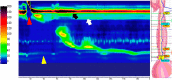

A 17-year-old girl was referred to our hospital with an inability to belch, while experiencing chest gurgling noises, and severe abdominal bloating. She reported having these symptoms all her life. A timed barium esophagogram revealed a moderate amount of bubbles in the esophagus and gastric fundus, which significantly increased after the examination. High resolution manometry revealed that the basal upper esophageal sphincter pressure increased with a rise in the cervical esophageal pressure. A pathological inability to belch is rare; at present, no specific name exists to describe the disorder. Further research is needed in this unexplored field.